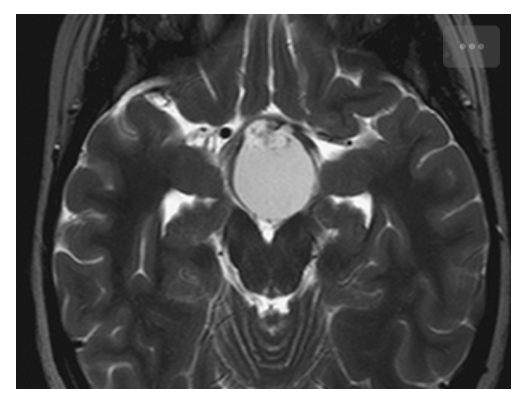

Craniopharyngioma. T2W axial image shows high signal within the cystic component of the mass. The punctate areas of low signal are due to calcification.